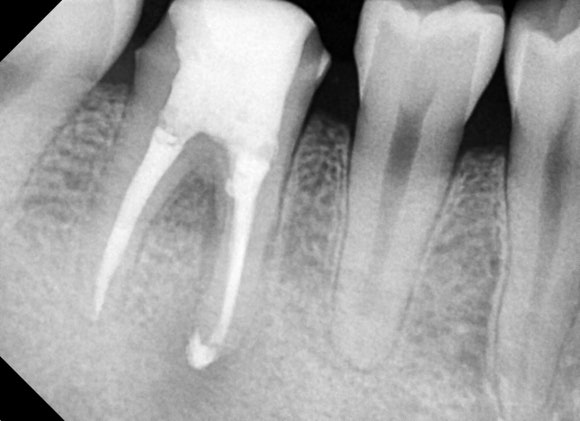

20241224

문제 치아를 확대하는 엑스레이를 찍어보니

뿌리 주위로 기분 나쁜 검은 그림자가

드리운 것을 확인할 수 있습니다.